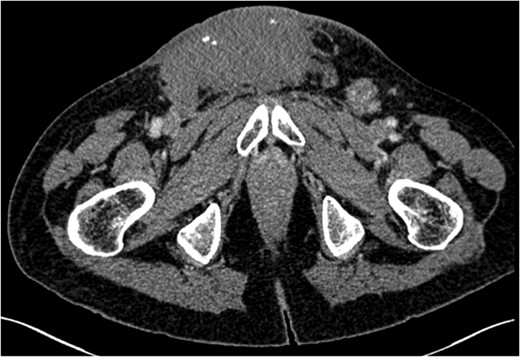

Seminomatous germ cell tumours characteristically affect men in their second-to-fourth decades, presenting as a testicular mass. Metastases when present are usually seen in para-aortic lymph nodes. These tumours are difficult to diagnose clinically and histologically when the presentation is unusual. We describe a seminoma presenting in a 61-year-old male as an inguinal mass with associated lymphadenopathy resembling lymphoma. Past medical history included ipsilateral cryptorchidism and orchidopexy. The tumour responded well to conventional chemotherapy.

Testicular tumours account for approximately 1% of all malignancies in men [1]. Up to 95% of testicular tumours are germ cell tumours (GCTs), which are subdivided into seminomatous and non-seminomatous tumours [2]. Histologically, seminomas may be further divided into three subtypes: classic, anaplastic and spermatocytic. Pure seminomas do not produce a specific tumour marker subset, but by definition have low levels of alpha-fetoprotein (AFP) and can have normal or mildly elevated beta-HCG (beta-subunit of human chorionic gonadotropin) [3]. Risk factors for the development of GCTs include cryptorchidism, Klinefelter's syndrome and testicular dysgenesis [4]. Testicular tumours commonly metastasize along gonadal vessels to the retroperitoneal lymph nodes [5]. Inguinal metastasis from a testicular seminoma is rare and likely related to previous inguinal or scrotal surgery causing disruption in normal lymphatic drainage [6]. We report a case of a massive seminoma presenting with primary inguinal lymph node metastasis in the absence of retroperitoneal lymphatic spread.

Testicular tumours account for approximately 1% of all malignancies in men, and they are the most common solid malignancy that affect males between 15 and 35 years old [2]. Up to 95% of testicular cancers are GCTs and the most common site for metastatic spread is the retroperitoneal lymph nodes. Inguinal lymph node metastasis is a rare occurrence and may be secondary to retrograde extension from significant retroperitoneal metastatic burden [5]. Primary involvement of inguinal nodes may be due to direct tumour invasion into the epididymis, breaching the scrotal wall or extension towards the vas deferens [7]. The large size of the tumour in our case suggests it is highly likely inguinal node involvement was via this route.

However, inguinal metastases have been reported in up to 10% of patients with a testicular tumour who have previously undergone orchidopexy or scrotal surgery [8]. It has been suggested that previous inguinal or scrotal surgery may lead to alteration in the usual patterns of lymphatic drainage. In our case, the history of orchidopexy for cryptorchidism could have been a significant factor for the absence of retroperitoneal lymphadenopathy despite the significant tumour burden at presentation. The overall risk of developing testicular cancer is greater in patients with previous cryptorchidism, occurring in 10% of GCTs [9]. Our case suggests that patients who have previously undergone inguinal or scrotal surgery may have alterations in normal lymphatic drainage leading to rare and atypical presentation of metastatic disease despite high tumour burden.

Ultimately, inguinal lymph node metastasis is a rare direction of spread for seminomatous GCTs. It may be secondary to direct extension of the tumour or alteration in the lymphatic drainage after previous inguinal or scrotal surgery. Although retroperitoneal lymph nodes are the most common site of metastasis in GCTs, alternative directions of spread should be considered in those patients who have undergone previous orchidopexy. Extensive imaging beyond CT for initial evaluation of retroperitoneal lymphadenopathy is unnecessary.